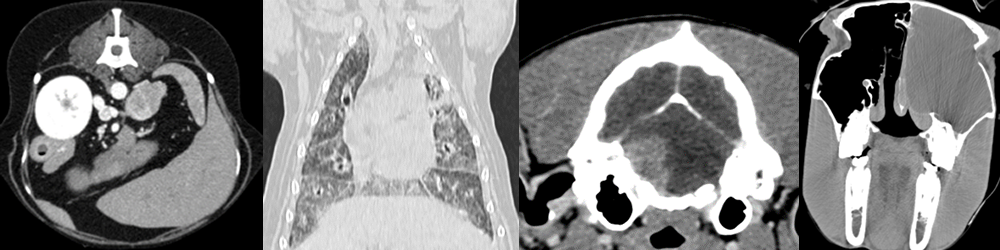

Walter De Wever

Keynote speaker

Contribution:

multiple contributions on Friday

Prof. dr. Walter De Wever

I’m chest radiologist with special interest in chest oncology and interstitial lung disease. I’m trained at the University of Leuven. I obtained my Doctoral Thesis in biomedical science entitled “Role of integrated PET/CT in the staging of Non-Small Cell Lung Cancer” in 2008. I’m clinical head at the radiology department of the University Hospitals Leuven. I’m professor at the Catholic University of Leuven.

I’m member of the European Society of Thoracic Imaging since 1999, member of the European Society of Radiology since 1999, member of the European Respiratory Society of since 2005. I’m chairman of Assembly 14 ‘Interventional Pulmonology and Imaging” of the European Respiratory Society. I was chairman of the imaging group of the Belgian Radiological Society from 2014 till 2018. I’m also Honored Member of the Radiological Society of South-Africa.

I’m author or co-author of more than 80 papers and book chapters. I gave many presentations on national and international congresses. I’m reviewer for many international journals.